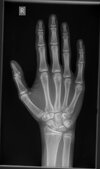

Male 193cm approx and 15.1 of years. im drinking daily 6L of raw cows milk and have been considering doing mk677 with cjc dac. any reccos? dont tell me stuff like ur already tall etc, i jut want to reach my max possible potential. For help, i attached a picture of my growth plates. they are fusing soon.

they’re basically fused, why bother if you’re already 193, you’re not going to see any difference in your life because of 194cm vs 193cm

basically means what? they are 100% open, just near the end. Some growth is still possible. 2 inches if im lucky ig